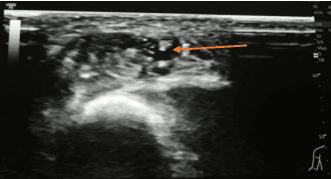

En aquellos casos de mayor complejidad en los que podamos dudar de la canalización accidental del vaso arterial podemos realizar una visualización en plano transversal. Este plano nos permitirá visualizar un punto hiperecogénico correspondiente a la guía metálica en el interior de la luz del vaso canalizado. De manera habitual podemos encontrar la imagen de la guía reposada en la zona inferior de la luz del vaso.

En las siguientes imágenes podemos observar la guía metálica en el interior de la luz del vaso izquierdo y posterior identificación del vaso arterial en la zona axilar mediante el uso del Doppler color. Esta simple comprobación nos permite asegurar la correcta canalización del vaso venoso con datos objetivos.